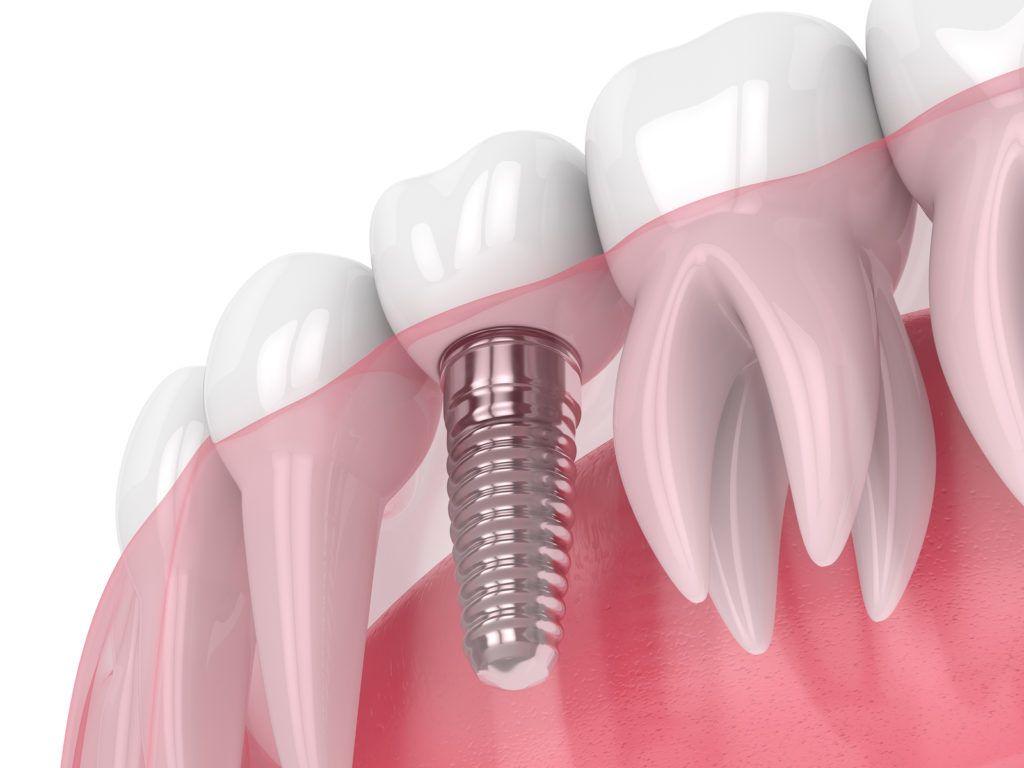

www.tmjandsleep.com.auDental Bridge - Procedure, Dental Bridge Vs Dental Implant

www.tmjandsleep.com.auDental Bridge - Procedure, Dental Bridge Vs Dental Implant

healthjade.nettooth implant healthjade phonetics pronunciation

healthjade.nettooth implant healthjade phonetics pronunciation